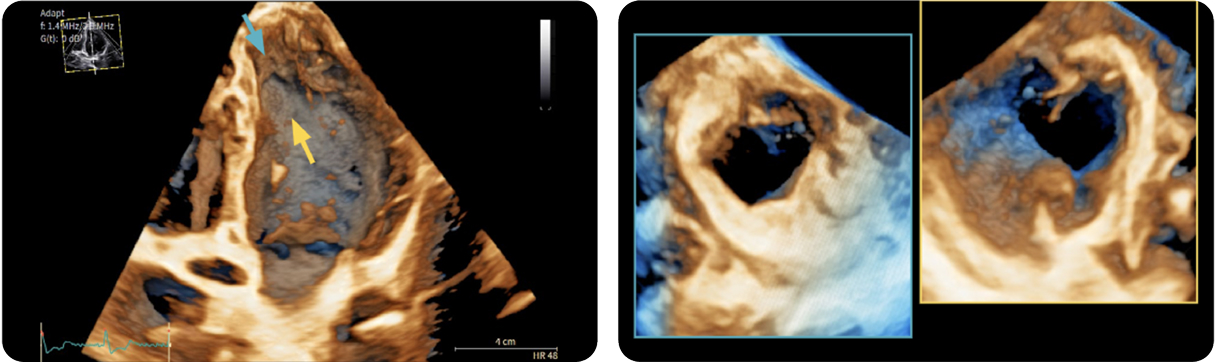

Dentro l'immagine

There is a world outside the stent mesh

Caso condiviso da Saima Mushtaq

Paziente con anamnesi di malattia coronarica e pregresso impianto di stent sulla discendente anteriore sinistra.

Per prima cosa, esamina l'intera scansione. Concentrati sul tronco comune e sulla porzione prossimale della discendente anteriore sinistra.